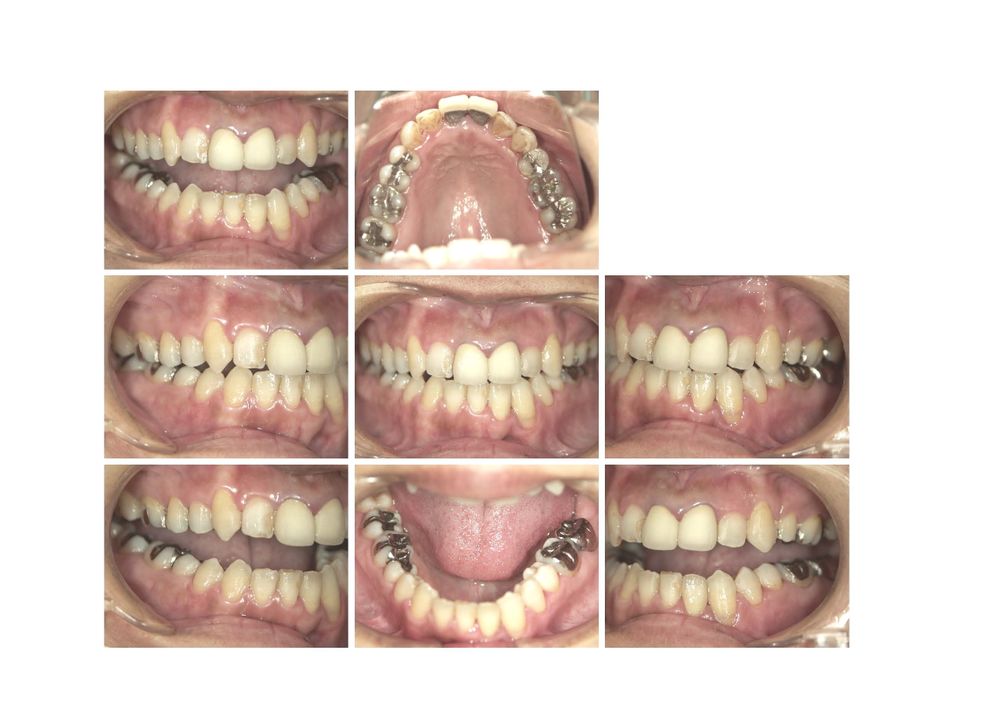

症例1

女性 61才 1年5カ月